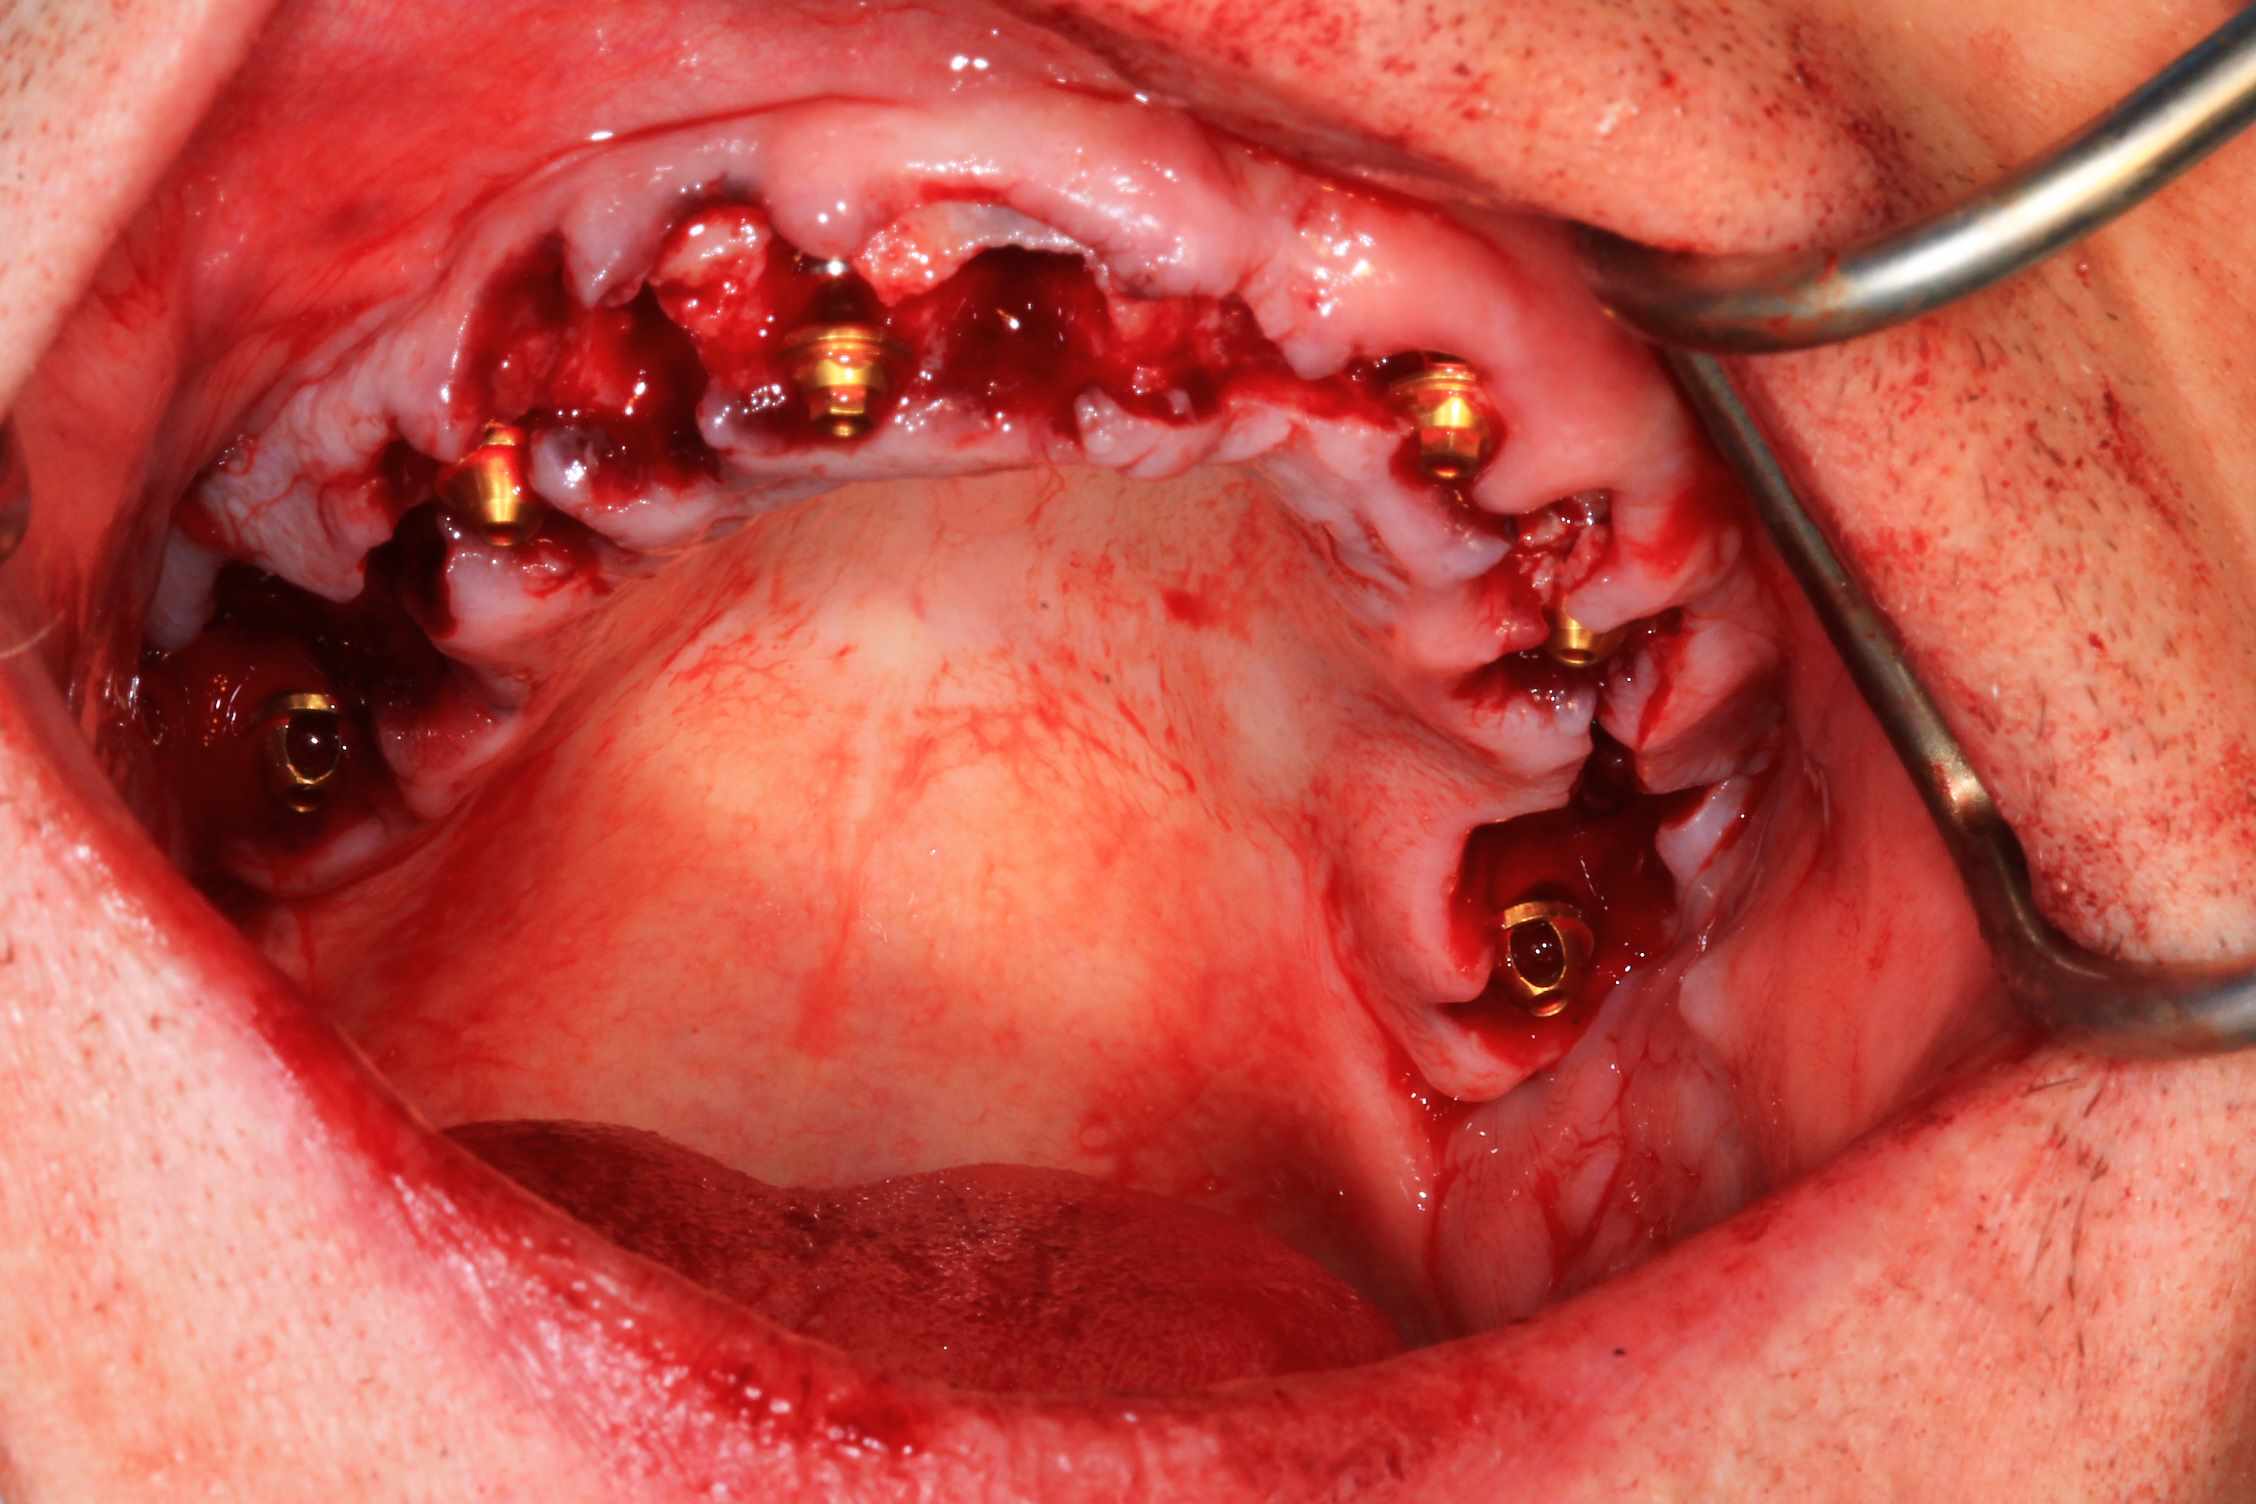

Le cas N°2 en images reelles :)

Guide métal avec support clavette, os assez fin : il est prévu un sticky bone complet : donc : lambeau avant extraction, positionnement du guide base et forage des clavettes, positionnement du guide implant, pose des piliers MU, controle des axes prothétique avec le guide pilier, collage des piliers prov sur le bridge a armature métal, occlusion nickel, sticky bone et PRF, sutures suspendues.

T’as quand même une sacrée déviation des implants / à la planification…..

Ça se voit déjà avec les implants posés à travers le guide de forage métallique qui est amha trop permissif

Et c’est confirmé par ton guide pour les piliers multiunits qui n’est même pas à fond (clavette antérieur pas mise….enfin certainement impossible à mettre)